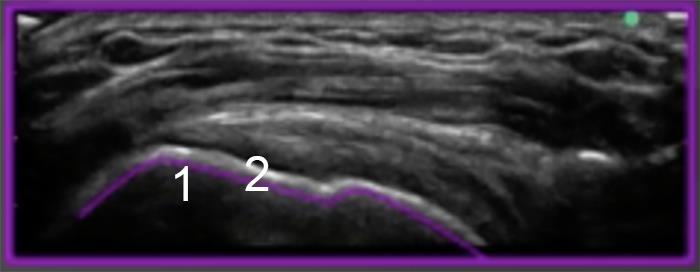

Shoulder Greater Tuberosity Anatomy 3 Longitudinal Bony Profile Image

1. Greater Tuberosity Middle Facet

2. Footprint of Infraspinatus/Supraspinatus